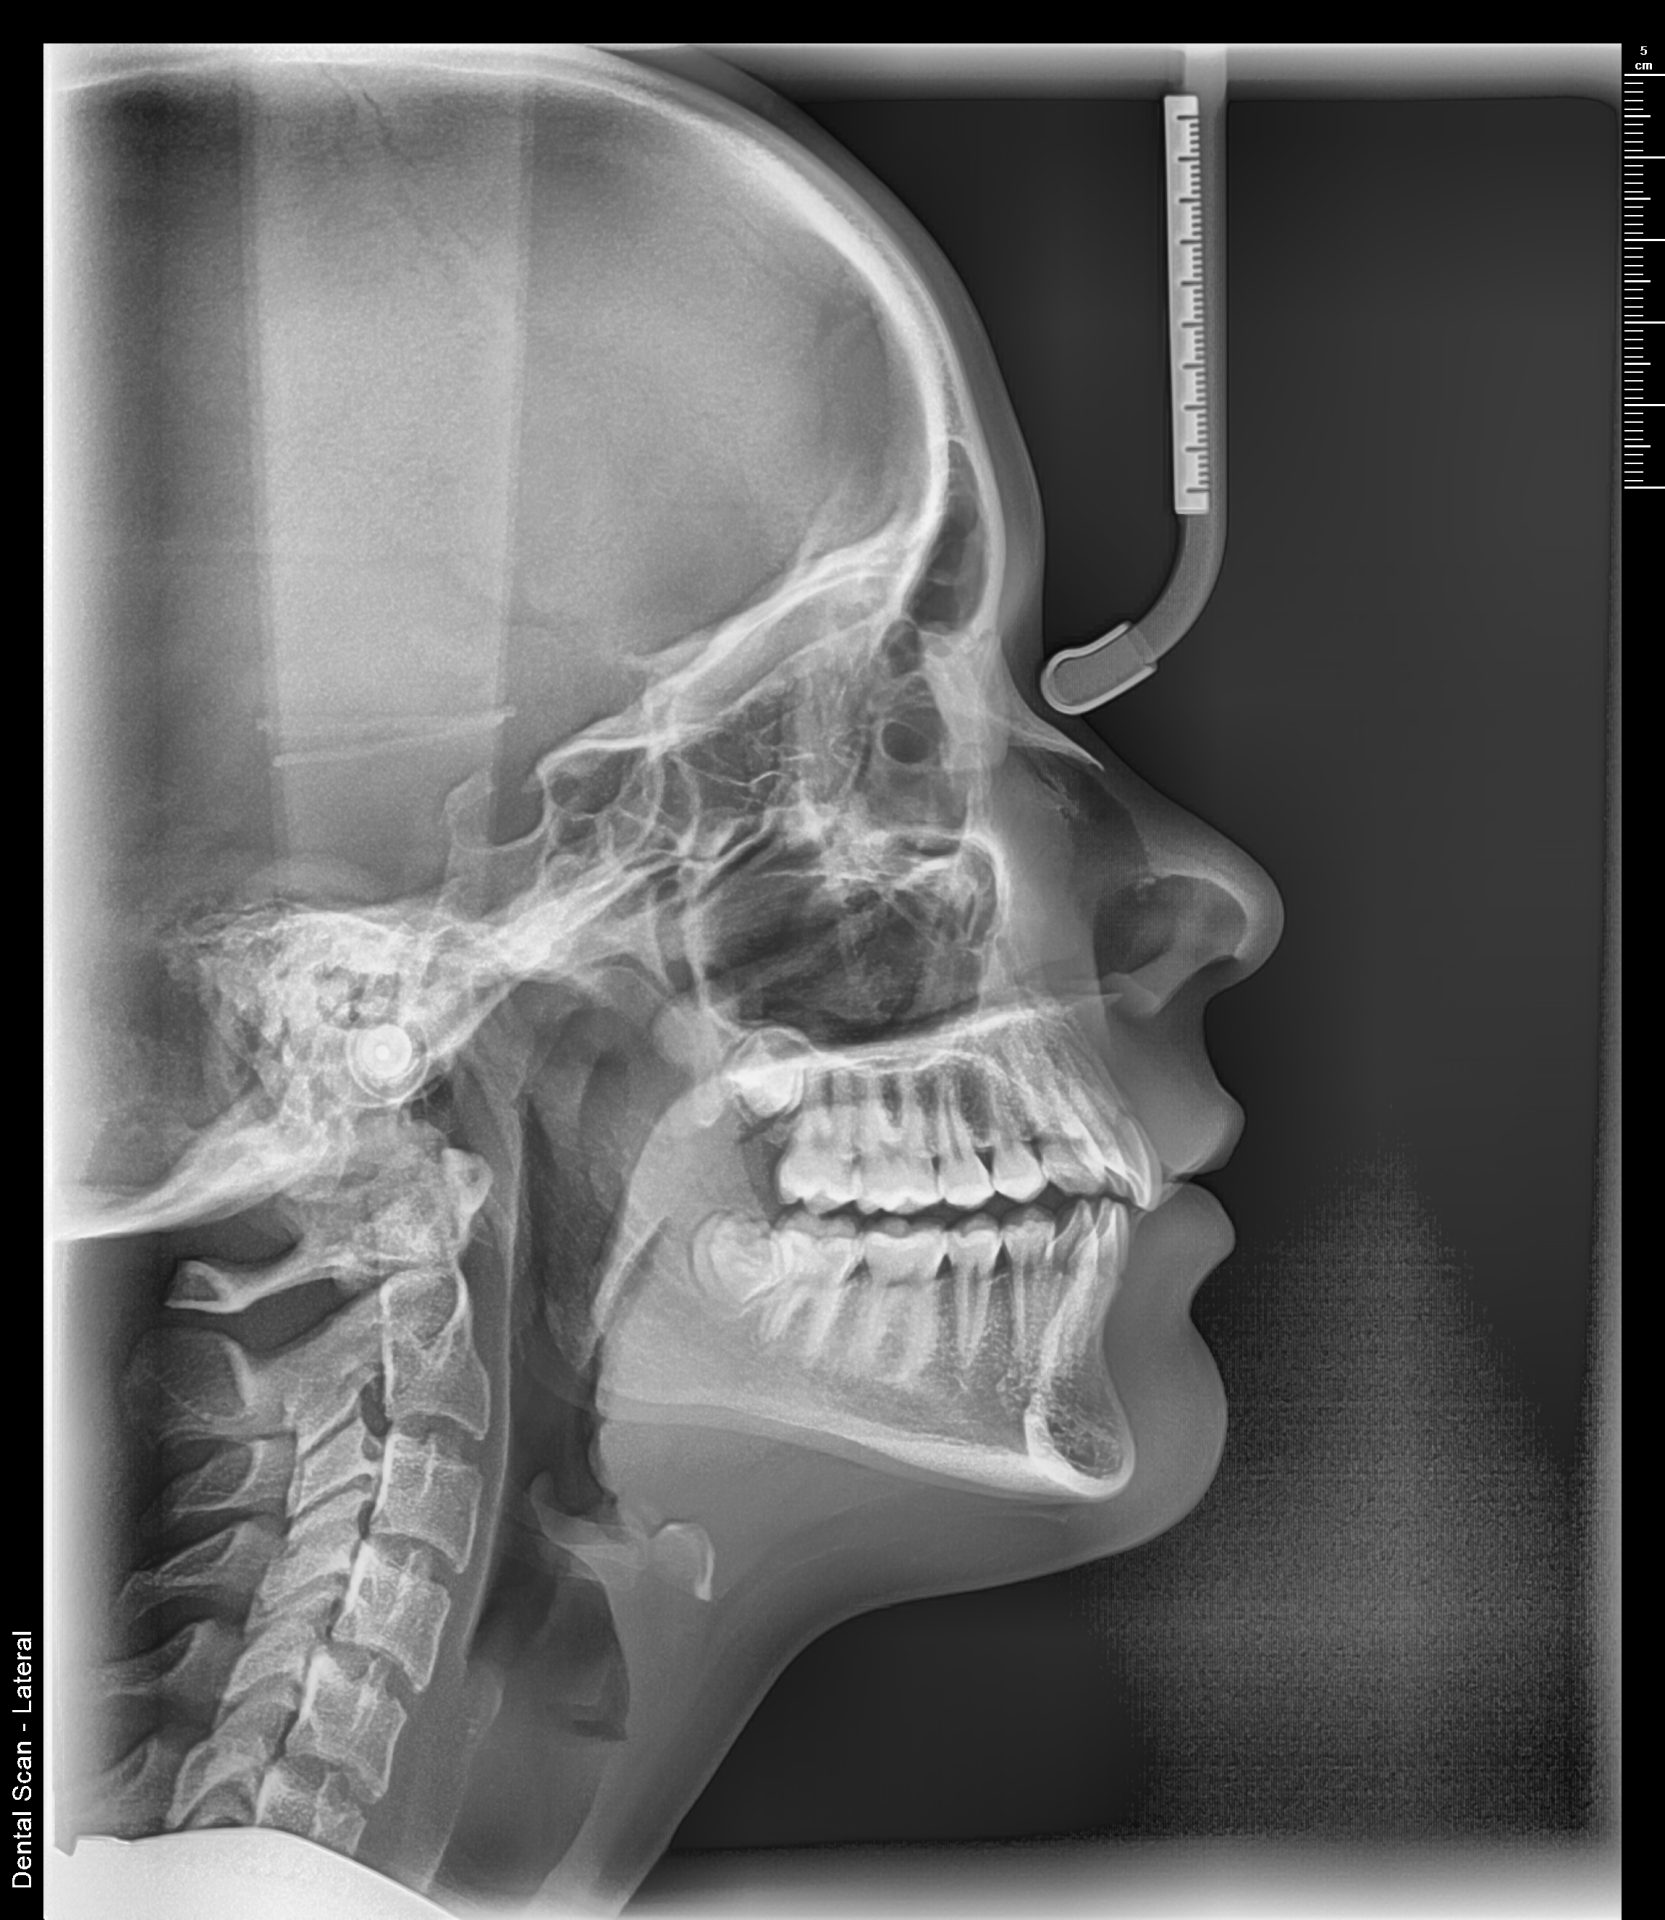

Telerendgen snimak – digitalni lateralni cefalogram za ortodontsku terapiju

Teleredgen snimak sa ortodontskom analizom

Telerendgen snimak predstavlja standard u ortodontskoj dijagnostici i osnovni je radiološki pregled koji se koristi za planiranje ortodontske terapije. Svaki savremeni ortodont zahteva telerendgen pre započinjanja terapije, posebno kada je u pitanju snimak za fiksnu protezu.

Šta pokazuje telerendgen snimak?

Digitalni telerendgen omogućava ortodontu da proceni:

1. međusobni odnos vilica

2. položaj i nagib zuba

3. skeletni tip pacijenta

4. pravac rasta vilice

5. odnos mekih i tvrdih tkiva.